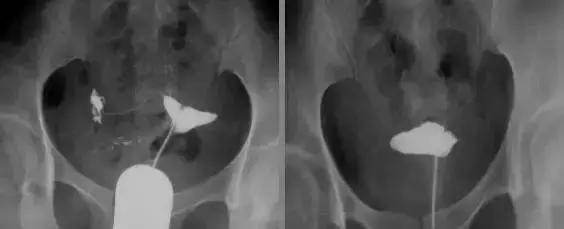

输卵管伞周粘连

输卵管间质部阻塞